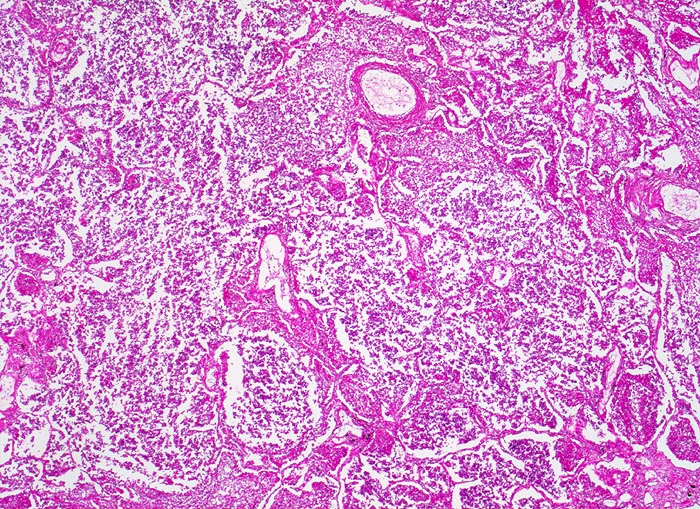

PathoPic – image database / PathoPic ID 4654 - Lobärpneumonie

Lobärpneumonie

Alle Alveolen sind gleichmässig und diffus befallen und im selben Stadium der Entzündung. Sie sind angefüllt mit fädigem Fibrin und neutrophilen Granulozyten.

Eine Lobärpneumonie tritt auf, wenn die Erreger die Alveolarräume so ausgedehnt und rasch befallen, daß sie erst vor anatomischen Grenzen (z.B. einem Lappenspalt) Halt machen.